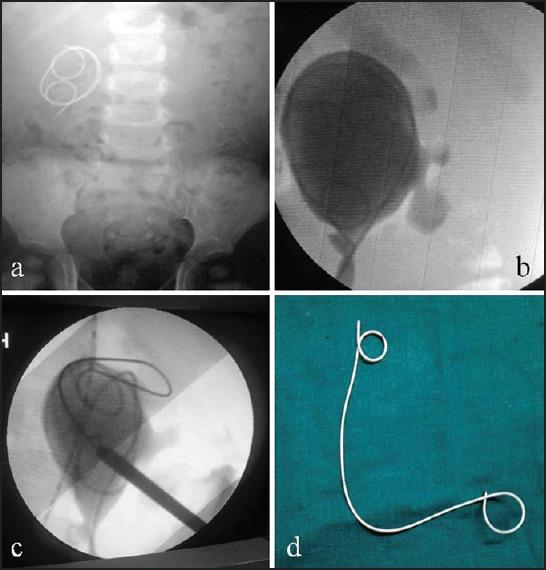

During the study period, January 2000 to December 2014 (a 15-year period), a total of 14 children underwent removal of forgotten/retained DJ ureteral stent. A combination of extracorporeal shock wave lithotripsy, cystolitholapaxy and percutaneous nephrolithotomy was done to free the DJ stent and extract it.

在研究期间,即2000年1月至2014年12月(15年期间),共有14名儿童接受了遗忘/留存DJ输尿管支架取出术。采用体外冲击波碎石术、膀胱碎石术和经皮肾镜取石术相结合的方法来取出DJ支架。